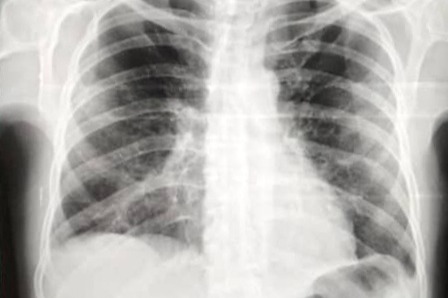

Mi padre Reinaldo Tirado, siempre ha sido asmático, presenta un cuadro de neumonía y la saturación de oxígeno en 84. Razón por la cual necesita ser hospitalizado de emergencia y recibir tratamiento para evitar empeorar.